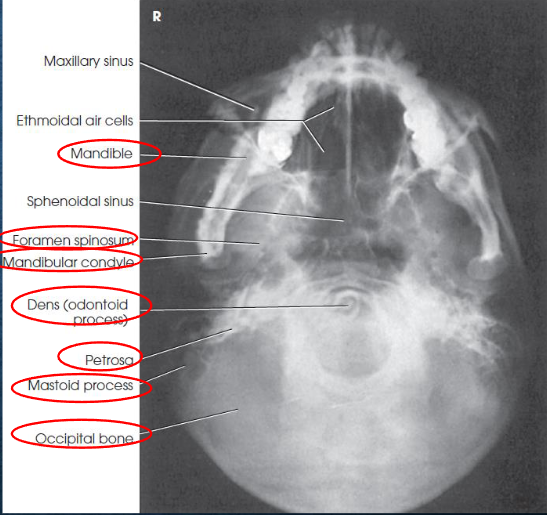

SMV (Schuller) skull

SMV (Schuller) skull image criteria

no rotation or tilt:

equal distance from lateral border of skull to mandibular condyles

symmetric petrous pyramids

penetration sufficient to demonstrate structures of cranial base

superimposition of mental protuberance over anterior frontal bone, indicating full neck extension

mandibular condyles anterior to petrous pyramids